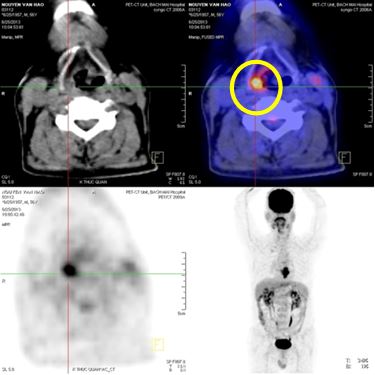

Bệnh nhân được chỉ định chụp PET/CT để đánh giá tình trạng u, hạch, di căn xa

- Kết quả chụp PET/CT vào tháng 6/2013:

- Tổn thương tăng hấp thu FDG mạnh đoạn thực quản 1/3 giữa, max SUV 10,72, kích thước 3x4,6x6,7 (cm)

- Tổn thương vùng xoang lê bên phải tăng hấp thu FDG mạnh, max SUV 9,47, kích thước 1,5x2x2,5cm

- Không thấy hạch trung thất, hạch cổ hai bên

- Các cơ quan bộ phận khác không thấy tăng hấp thu FDG bất thường

Hình 3. Hình ảnh PET/CT: Khối u thực quản 1/3 giữa - dưới (màu đỏ), khối u vùng hạ họng (xoang lê) phải (màu vàng.